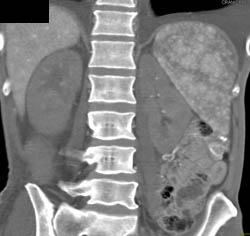

Gastric Cancer